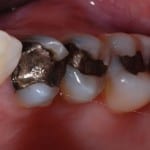

A filling will plug the hole and stop future pain or discomfort. There are a variety of materials, the most common of which are amalgam (silver) and composite (white) although we are increasingly using highly aethetic and strong ceramic fillings made with our CEREC system.  We are the only practice in Harrogate and Knaresborough who are able to offer this technology

Larger cavities are best restored using all ceramic fillings made using our unique CEREC system. These give the ideal combination of great aesthetics and strength for long lasting restorations